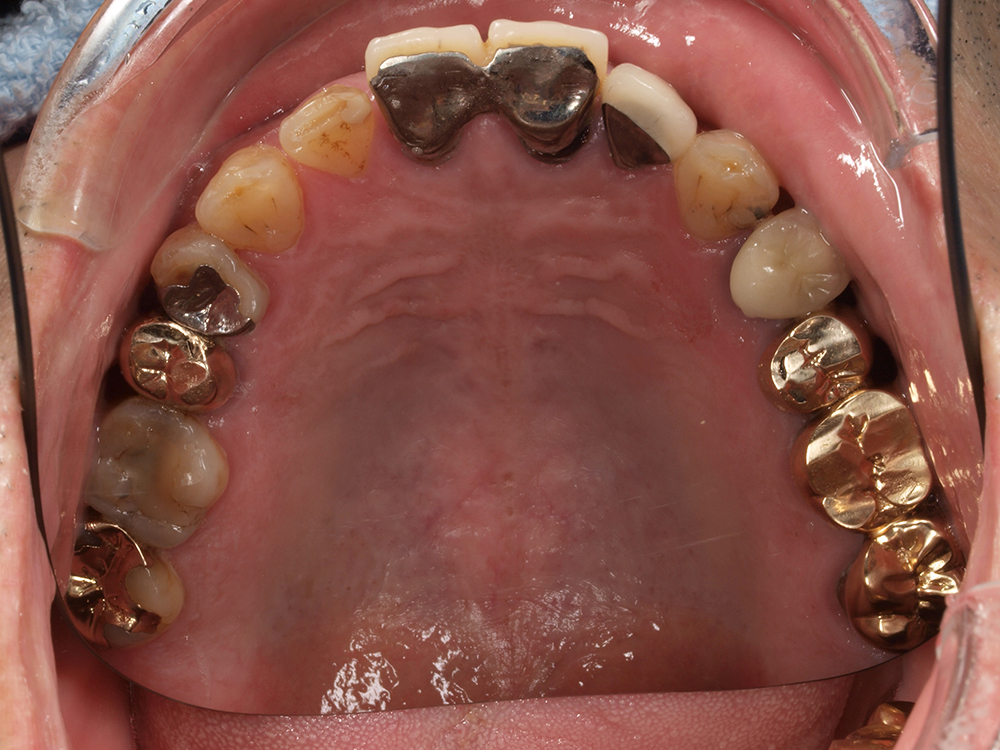

53歳 男性

- 主訴

- 全然噛めない。上の歯が取れてきた

- 処置内容

- 上顎:8本 下顎:2本

- 治療費用

- 上顎:約320万円(税込)、下顎:約160万円(税込)

- 治療期間

-

上顎:1年(仮歯まで8か月)

下顎:8か月(仮歯まで5か月)

- リスク

- 上部構造物、仮歯の破折、術後の腫れ(3日)、人工歯根脱落リスクがあります